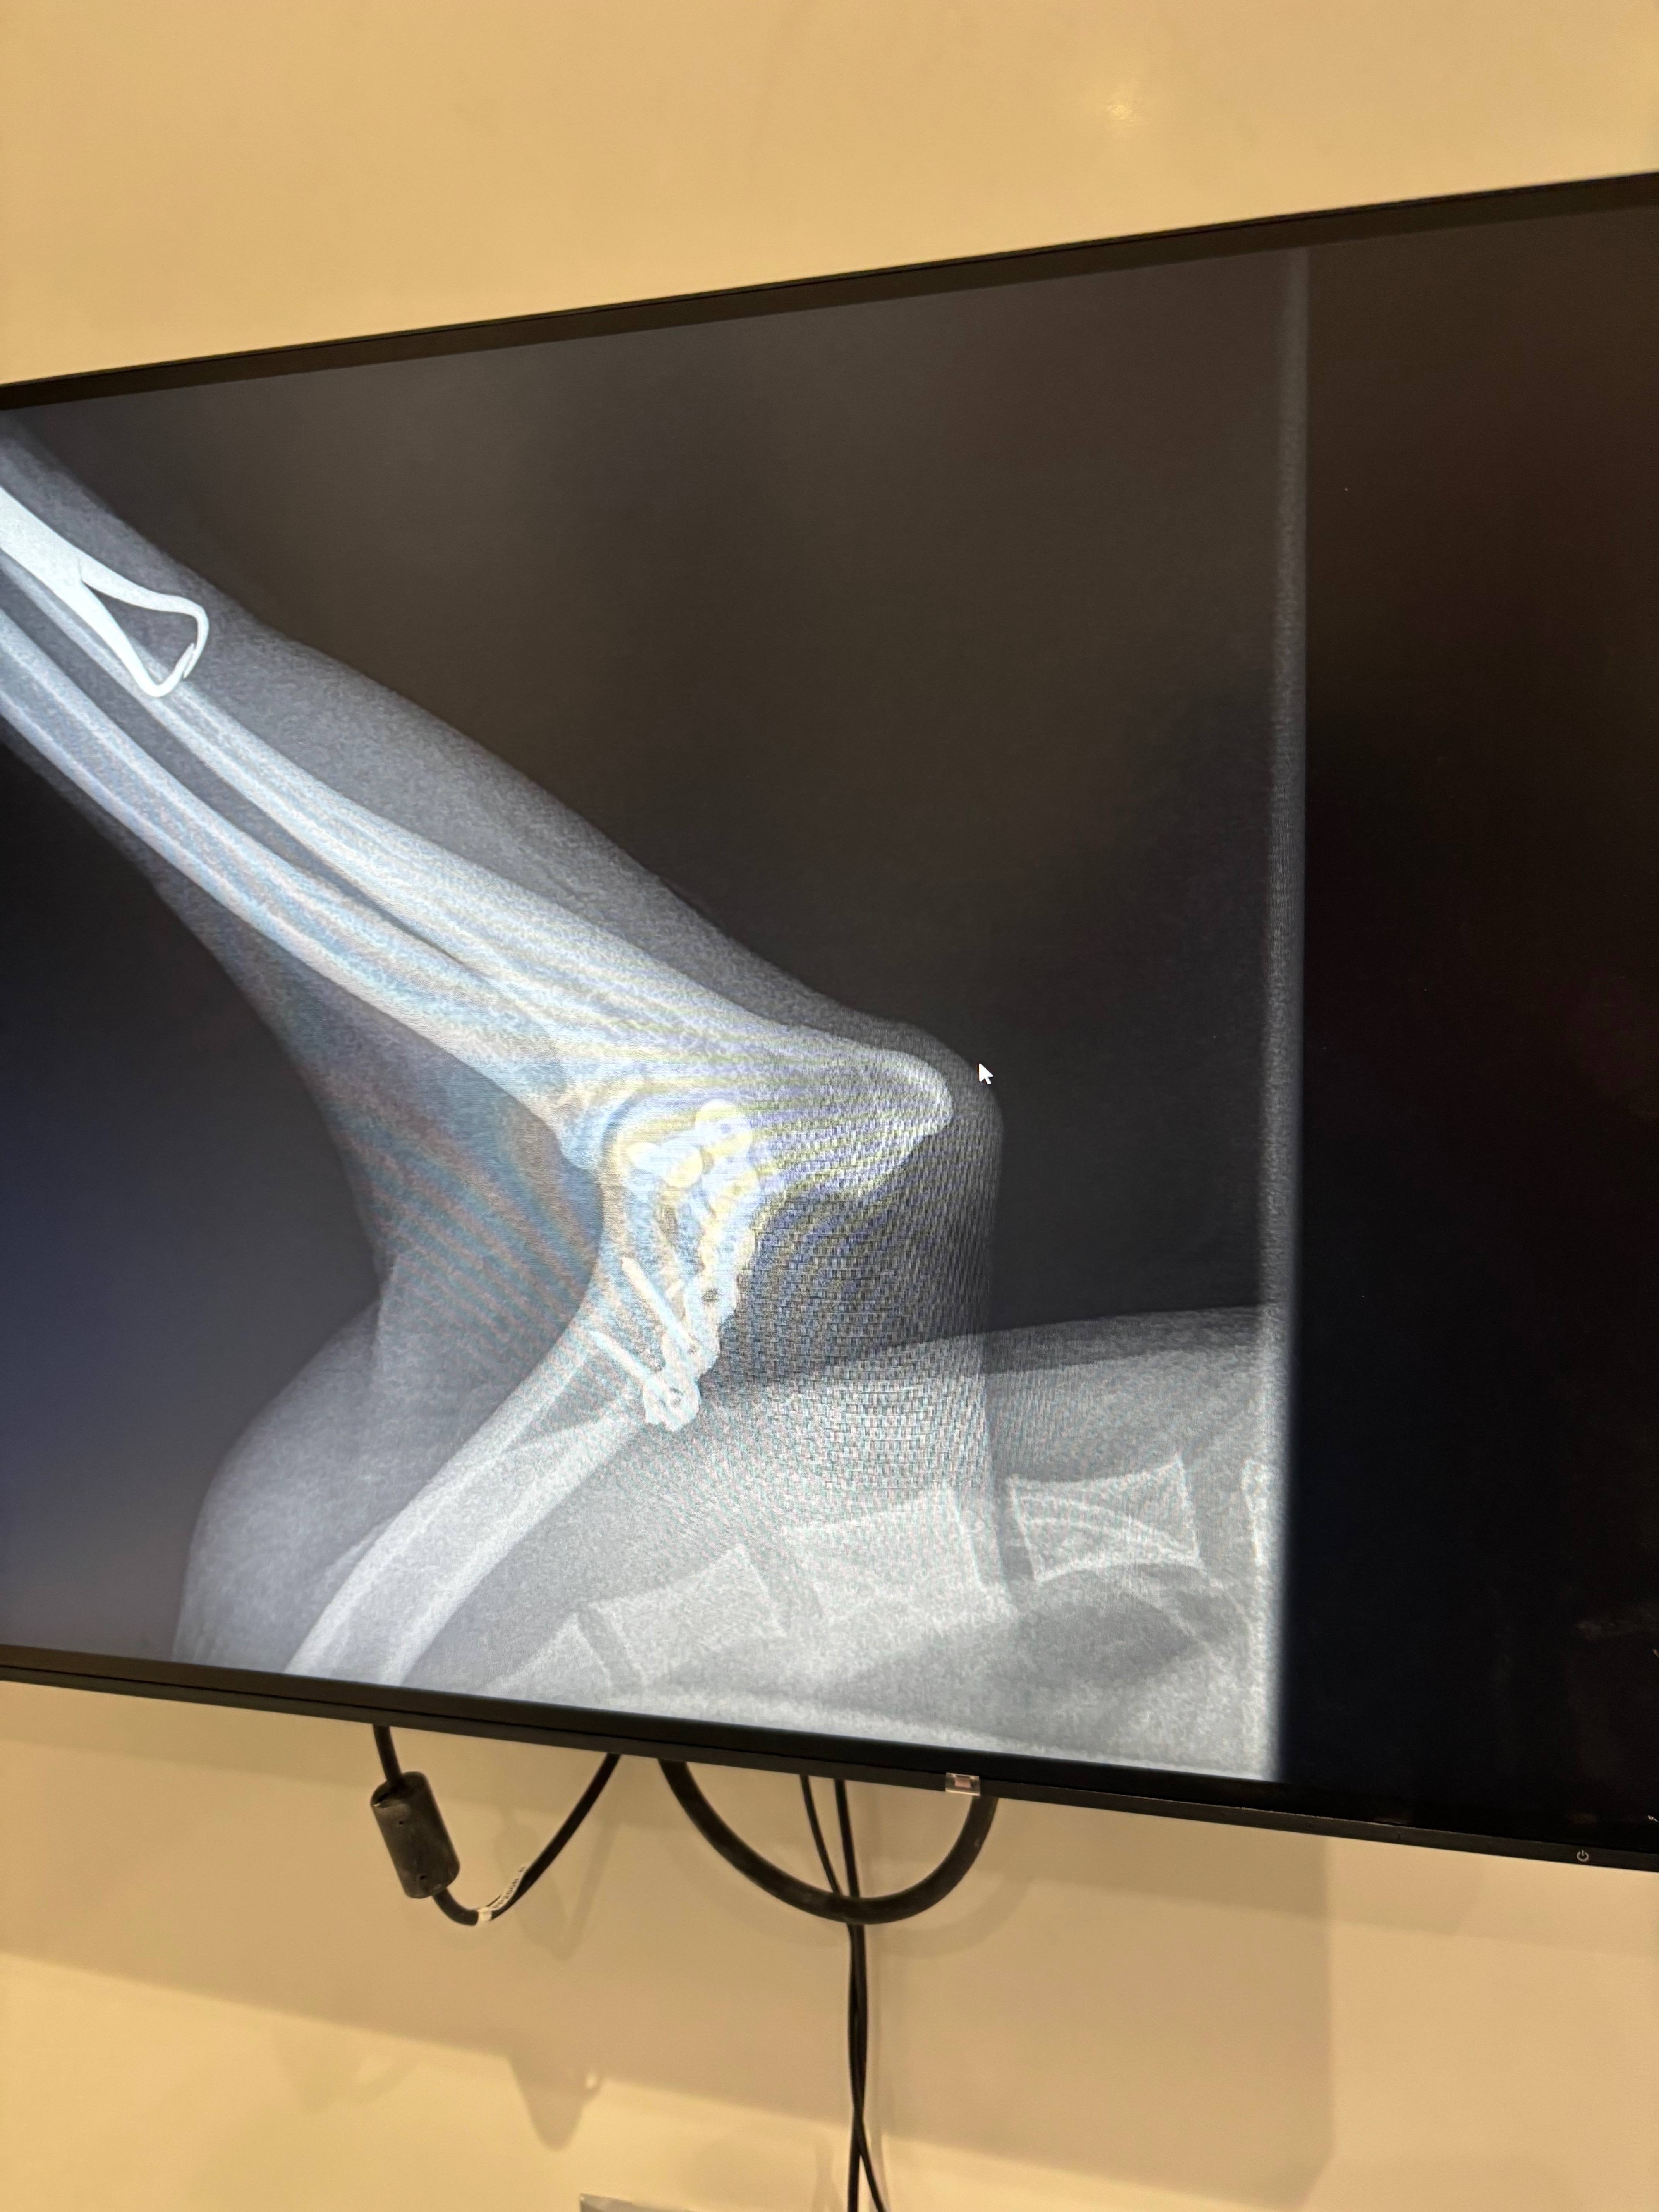

So yesterday evening (Saturday 6/9/25) my parents dog (Ralphie) had a serious accident out on his walk, which meant he was rushed to an out of hours vets where he’s had X-rays done which are showing he has a serious fracture on his elbow which means he will either need a big rebuild or leg amputated. So far the vets have said it’s going to cost £3.5k to keep him at the vets until Monday for his out of hours care and sedation/ pain relief . Then come Monday Ralphie will be taken back to his original vets where we can hopefully make a plan moving forwards. Either option is going to be highly expensive whichever route we go down, It would be be greatly appreciated if people could help donate toward Ralphie's Road to recovery ❤️‍ Even if you can just donate a couple of quid, every little helps and will make things a lot less stressful for the family at this hard time.

8/9/25- *update* Ralphie has been moved to Poole to see a specialist surgeon. He’s had Ct scans this morning which show he has a Y fracture, the surgeon has operated and done this kind of surgery before which was successful, so nice to hear some positive news. If all equipment is available today E.g (nuts, bolts, screws, plates) then surgery may go ahead today.